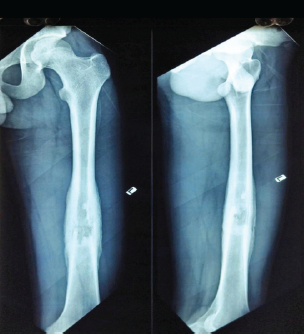

Challenges in Diagnosing Diaphyseal Osteosarcoma – Importance of Strong Clinical Suspicion and Biopsy Technique: An Illustrative Case Report

V Balaji , Mohammed Tavfiq , Subalakshmi Balasubramanian , J K Giriraj Harshavardhan , Sabare Naaharaaj

………………………………p.184-190